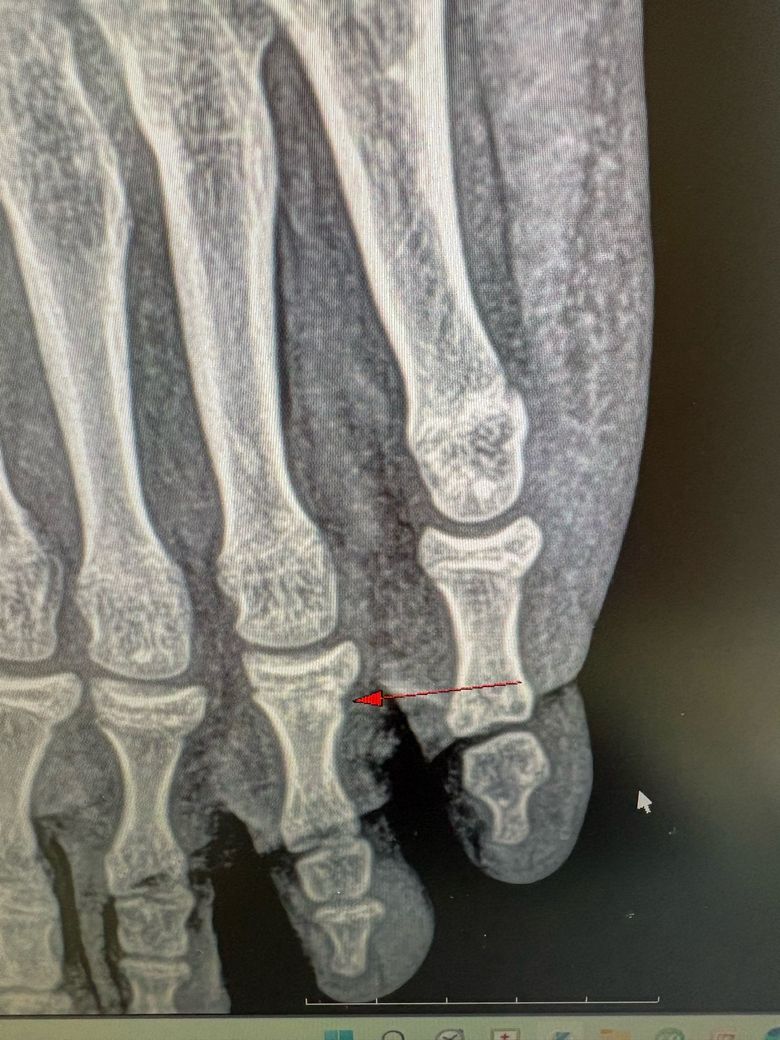

동생 발가락이 골절인가요? 봐주세요

동생이 학교에서 친구랑 놀다가 사이가 않좋은 상황에서 집에와가지고 분풀이를 책가방에 하려다가 그만 벽을 차는 바람에 아파서 울고 난리를쳐서 다음날 정형외과 갔더니 골절?이라해서요 제가봤을때는 발가락사진에 파인부분이 하나라면 그러려니 하는데 발가락 사진 전체가 파여있어서 골절이 아닌거 아닌가요??? 동생만 지금 고생하고 병원비만 깨지고 있습니다

사진이 파여 보인다고 해서 "골절이 아닌 건 아닙니다" 발가락은 "미세.금발골절"이 X-ray에서 그렇게 보일 수 있어요.

차는 충격이면 "타박 + 골절이 함께" 오는 경우도 흔합니다.

통증.압통이 뚜렷하면 치료가 필요한 골절일 가능성이 높습니다.

올려주신 사진이나 전문의 소견을 참고했을 때 골절 가능성이 높겠는데요, 발가락과 같은 작은 뼈 구조는 골절 발생시 관찰이 어렵고 발의 구조 자체가 크게 뒤틀리지 않아 질문자분께서 보셨을 때에는 다른 발가락과 구별이 크게 되지 않는 것으로 생각됩니다.

우선 사진만으론 판단을 하긴 어렵지만 골절 소견이 있었다면 현재로썬 골절을 충분히 의심해볼 수 있습니다.